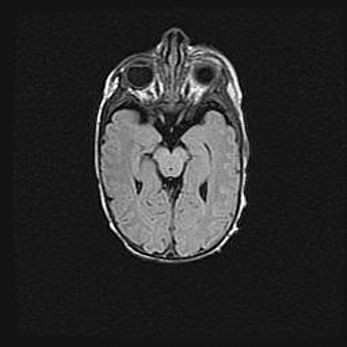

Мальформация Денди-Уокера. Киста задней черепной ямки.

Агенезия мозолистого тела.

Возраст: 2,5 месяца

Вес: 2420 г

Пол: женский

Окружность головы: 37 см

Срок гестации: 32 недели

Мальформация Денди—Уокера — редкий вид патологии ЦНС, представляющий собой врожденный порок развития каудального отдела ствола и червя мозжечка, ведущий к неполному раскрытию срединной (Мажанди) и латеральных (Лушка) апертур IV желудочка мозга. Для этогно синдрома характерна триада симптомов: гипотрофия червя мозжечка и/или полушарий мозжечка, кисты задней черепной ямки, гидроцефалия различной степени. В 70% случаев порок сочетается и с другими аномалиями головного мозга, в частности с агенезией мозолистого тела.